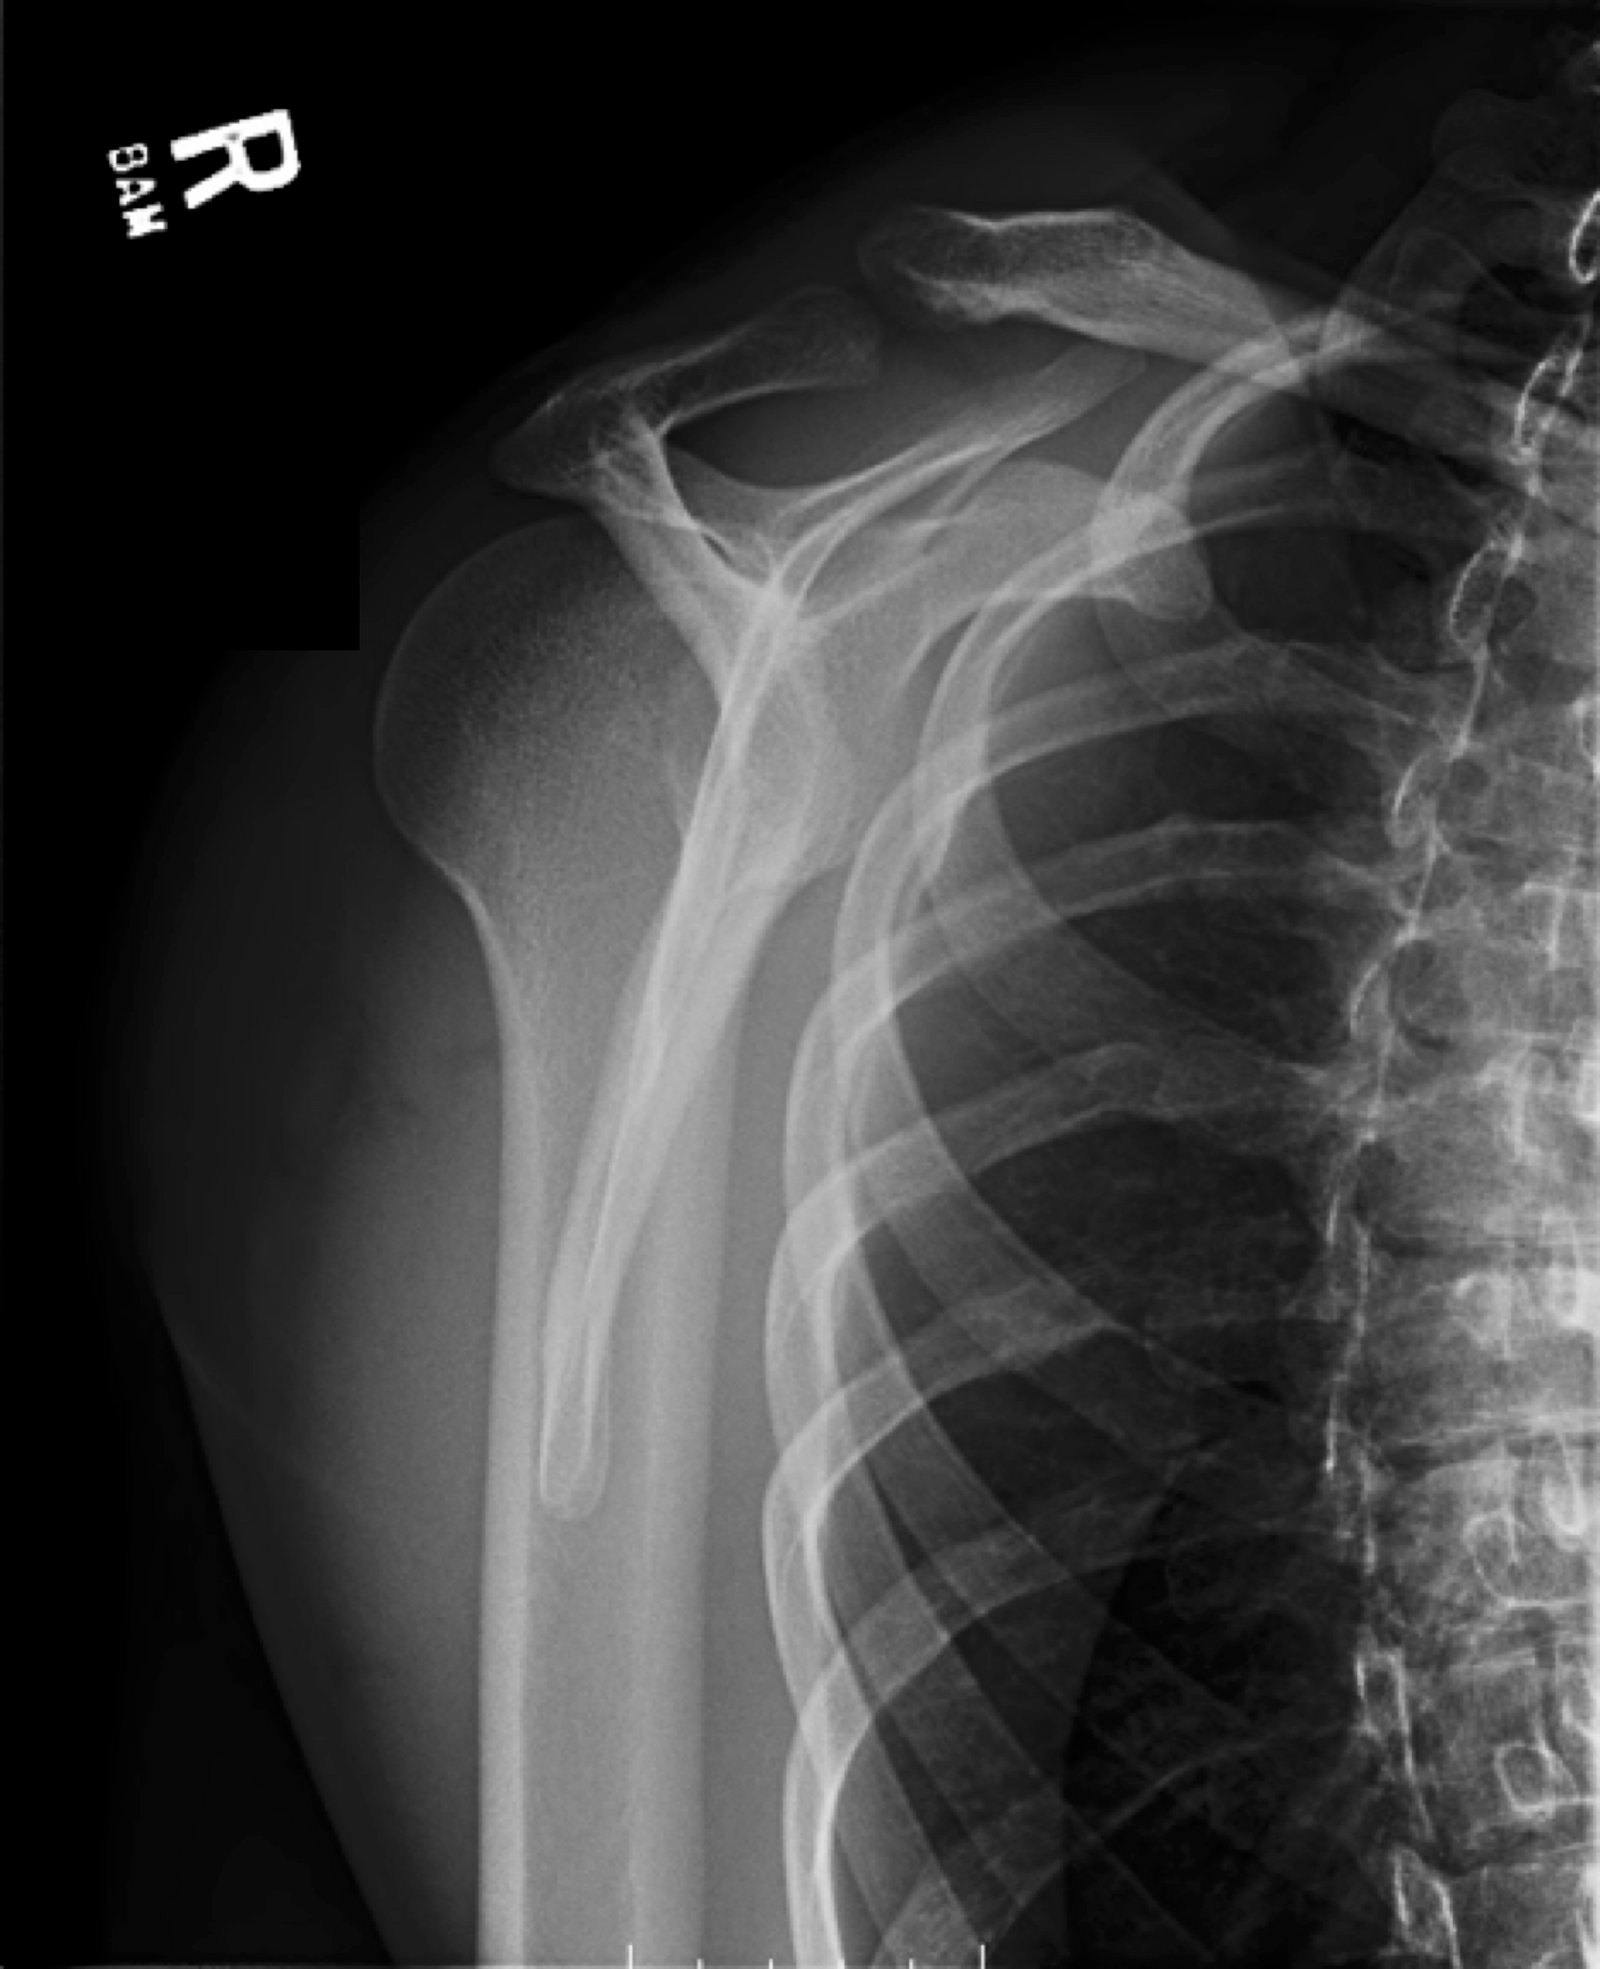

Posterior Shoulder Dislocation, Y View XR. JETem 2017